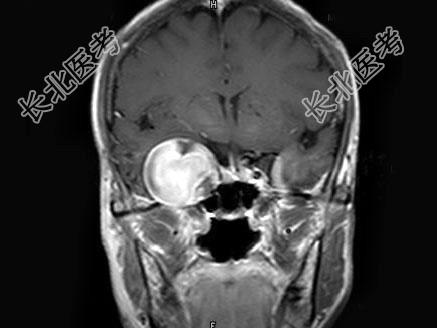

- 单项选择题女,62岁, 头痛数年,头颅MRI检查如图, 最可能的诊断是 ( )

A、脑膜瘤

B、动脉瘤

C、脑出血

D、转移瘤

E、未见异常